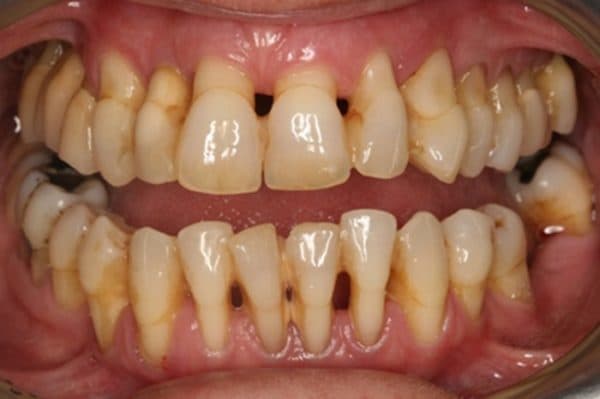

Do lợi bị tụt nên giữa các răng hình thành khoảng cách